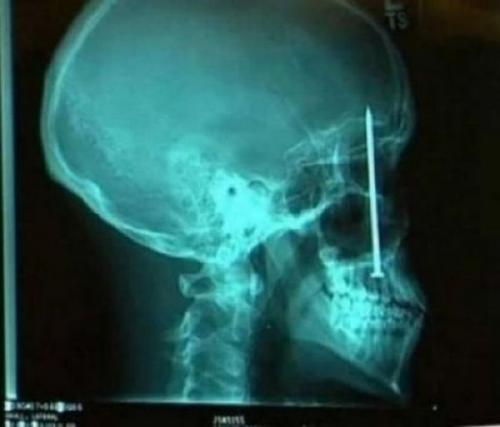

Предметы, которые можно обнаружить в человеке благодаря рентгену

Внутри человека с помощью рентгенологического оборудования можно обнаружить массу оригинальных предметов, причем порой даже несовместимых с жизнью.

Гвоздь